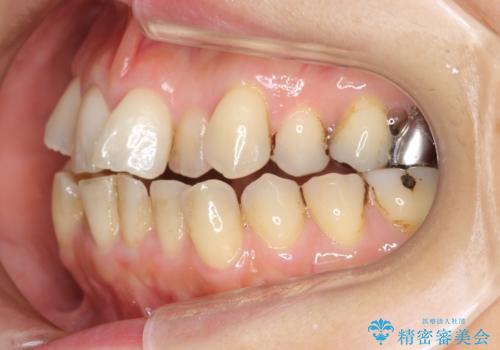

前歯は開咬傾向であり、小臼歯から大臼歯にかけてもオーバージェットは非常に小さく咬耗していました。

途中再評価を行い、矯正用のミニスクリューを用いて奥歯を遠心移動し、前歯の出っ歯傾向を改善しました。

左上12の段差についてはここまで直すのにもかなり時間がかかりました。インビザライン単独では限界があると説明し、ワイヤーの部分矯正もご提案しましたが、患者様のご希望によりインビザラインでできるところまで頑張るということで4回ほどリファインメントを行いました。